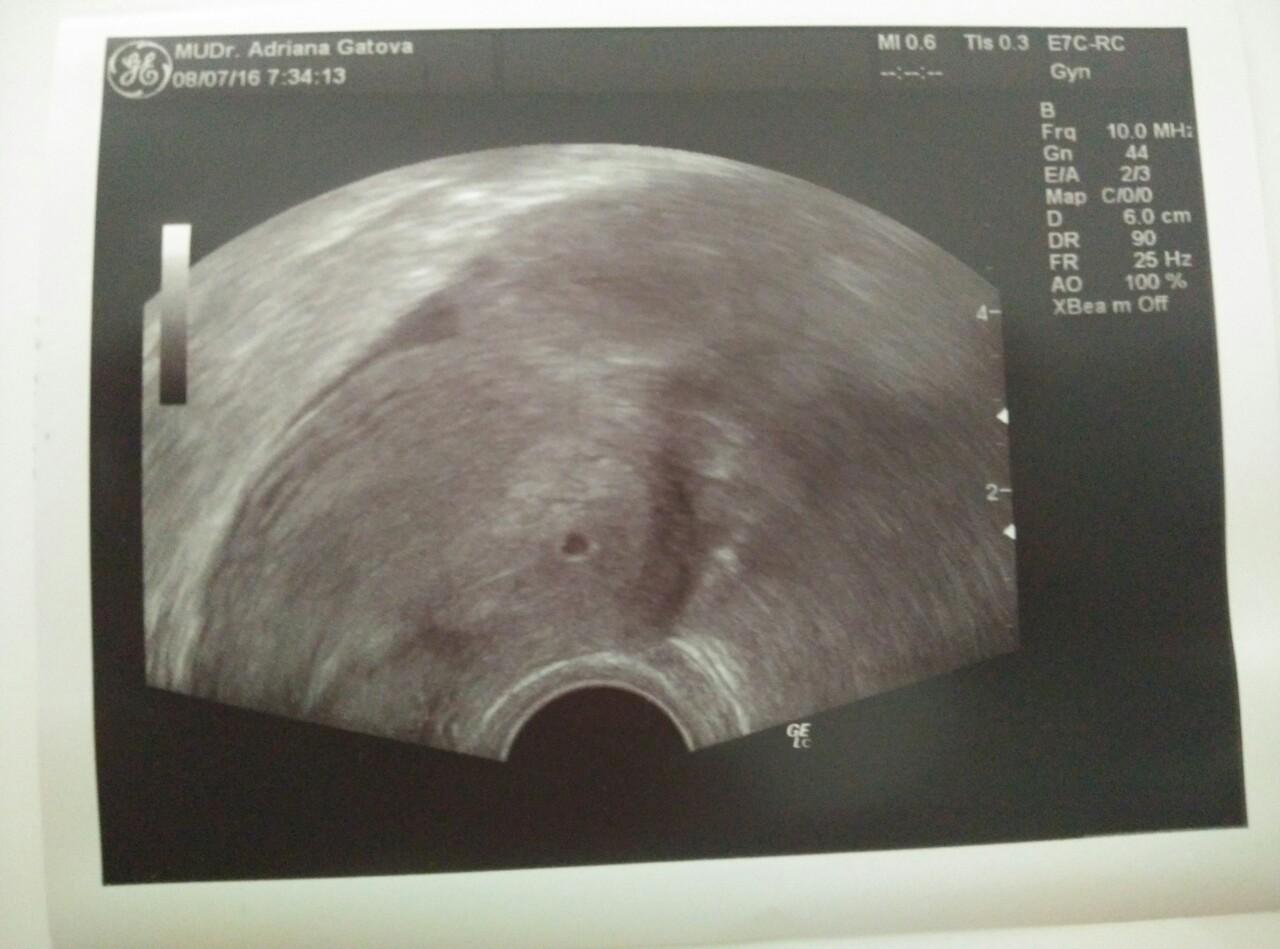

Dievčence ja dnes takto u svojej doktorečky 😃 najšťastnejšia na svete sa citim 😍😍😍😍💜